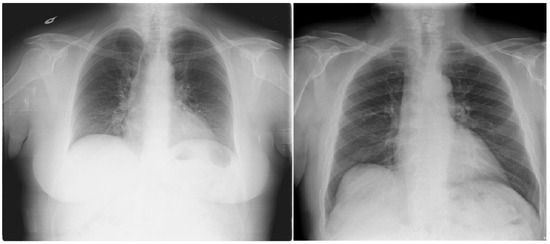

The dataset comprises 112,120 X-ray images with disease labels from 30,805 unique patients [21]. The samples from the CXR NIH dataset are shown in Figure 3. Disease labels were extracted from radiology reports using NLP, achieving over 90% accuracy and supporting weakly supervised learning.

Figure 3.

CXR NIH dataset samples [21].

In order to gain a representative insight into the subject matter, the study utilized the CXR NIH dataset. This is a large-scale hospital-grade database comprising 108,948 frontal-view CXR images from 32,717 patients, and it has gained recognition as a valuable resource within the field [22]. The dataset includes images labeled for eight common thoracic diseases using an NLP system applied to radiology reports. While this automated approach enables scalable and consistent labeling with over 90% estimated accuracy, it may occasionally produce ambiguous or incorrect labels.